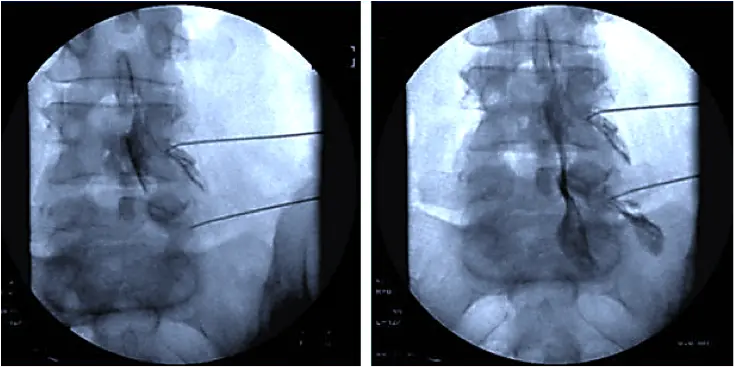

Процедура выполняется под местной анестезией под контролем электронно-оптического преобразователя. В отличие от хирургического вмешательства, при пункционной фасетопластике отсутствует эффект деструктивного воздействия на дугоотросчатые суставы. Использование рентген-навигации в процессе лечения исключает повреждение сосудисто-нервных образований позвоночного столба.